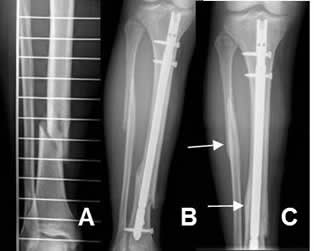

Fig 81. Remodelación.

A: Rx AP. Fracturas espiroideas del peroné y la tibia.

B: Rx AP. Reducción tibial con clavo de Kuntcher.

C: Rx AP. Después de 16 meses hay completa cicatrización, con formación de callo óseo compacto.